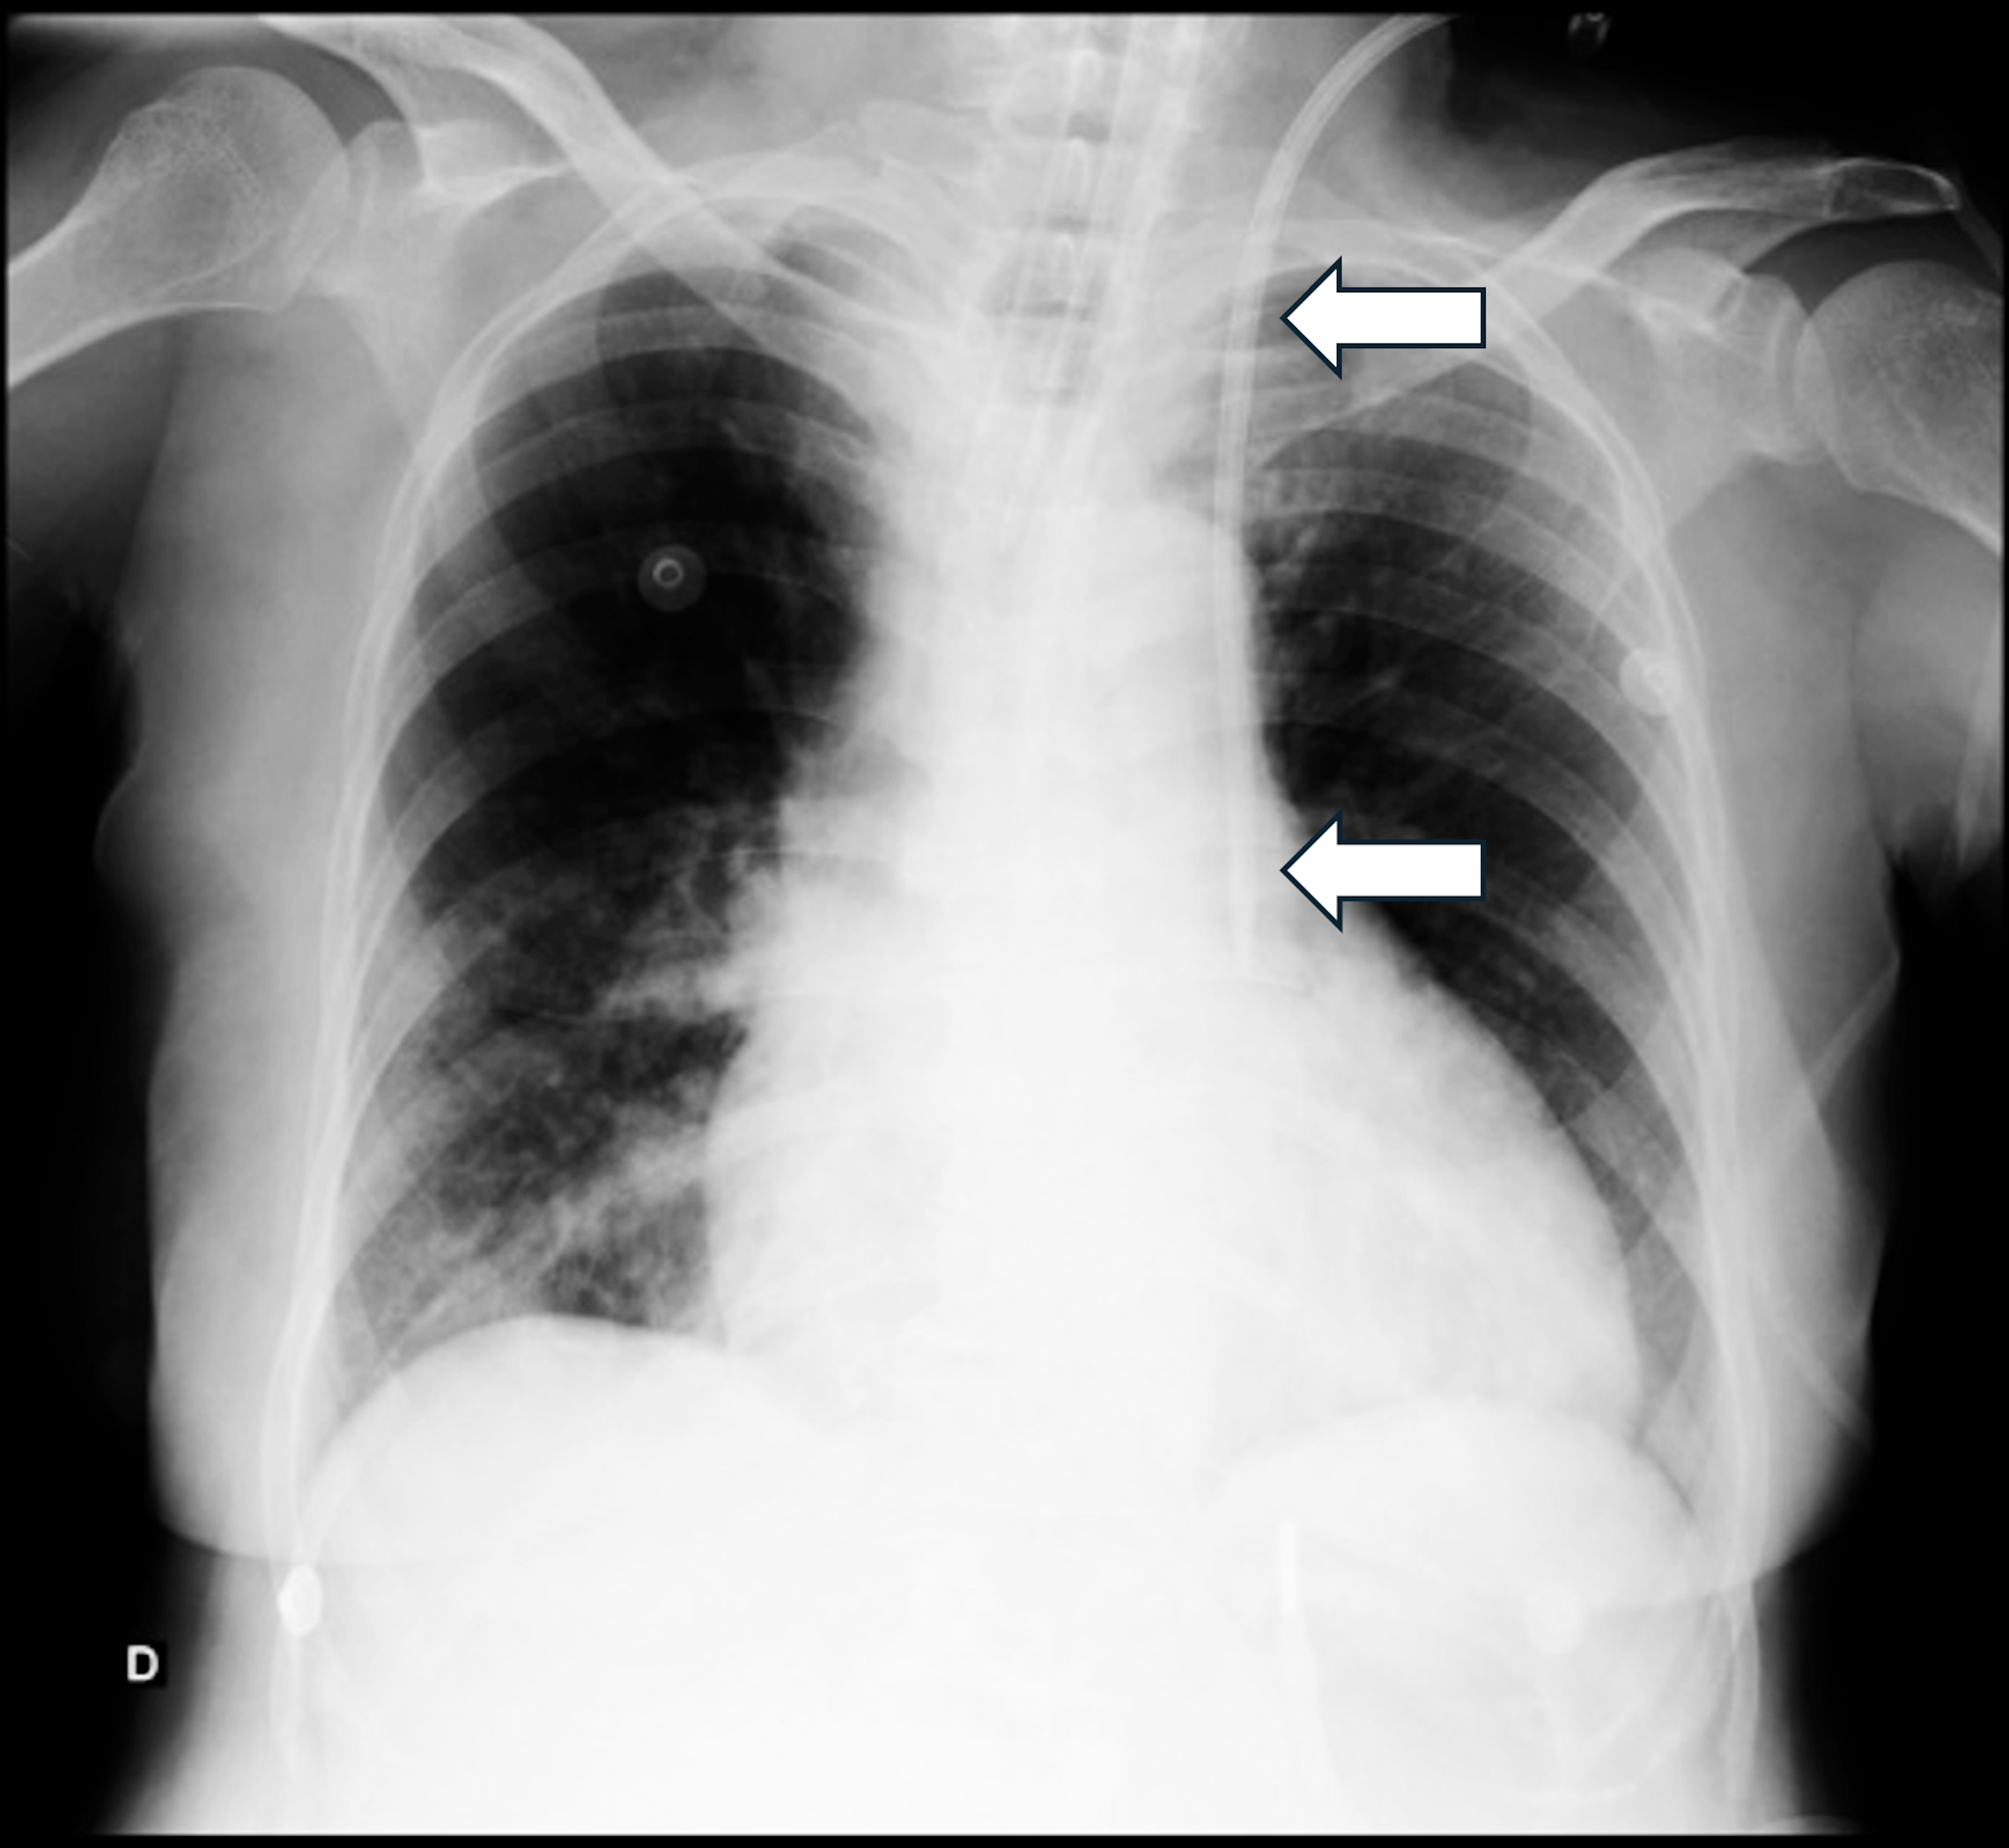

Blunt Thoracoabdominal Trauma with Multiple Injuries in a Motorcycle Accident: A Complex Case Report in the Emergency Room

Ana Paula de Carvalho Miranda Rosati Rocha, Luis Fernando Rosati, Marcos Alvin Abbade, Ana Luiza de Carvalho Miranda Rosati Rocha, Vinícius Alves Carneiro Lima